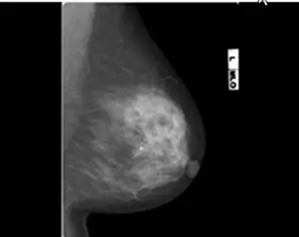

乳房X線撮影装置デジタルマンモグラフィ

この度、マンモグラフィー装置を富士フイルムAMULET Innovalityに更新しました。

新しい画像処理技術により、従来より少ない放射線量で高画質の撮影をすることができるようになりました。また、自動減圧機能「なごむね」により、乳房の厚みが変化しない範囲で自動で圧迫圧を減圧し、痛みを低減することが可能になりました。

当院では、検診マンモグラフィ撮影認定を5名が取得しており、撮影は女性技師が対応しています。また3年毎のマンモグラフィ検診施設(日本乳がん健診精度管理中央機構)の認定更新を実施し精度管理にも努めています。